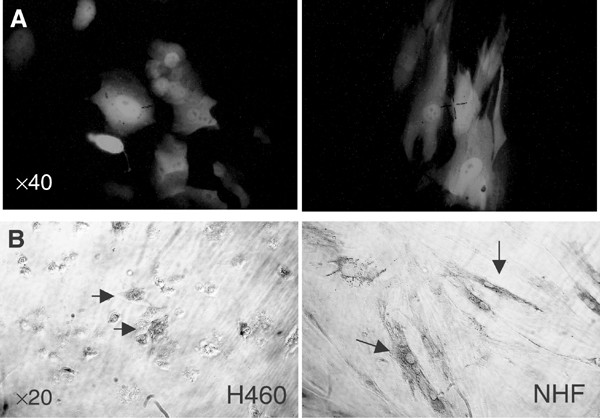

To study the possibility that under conditions of chemotherapy enhanced Ad TRAIL-induced H460 cell killing the sensitivity to normal cells could also be altered, we treated NHF cells in the same way and determined cytotoxicity. For this purpose, first the infection efficiency of NHF was examined. Figure 6A shows a considerable level of AdGFP infection at MOI 100 in NHF cells of approximately 20%, whereas H460 cells demonstrated an infection efficiency of around 70%.

Infection with AdTRAIL eradicated most of the H460 cells but left the NHF intact as indicated by the few remaining cells that were either positive or negative for TRAIL expression in H460 cells as determined by immunohistochemistry (Figure 6B). Subsequently, the effect of combined chemotherapy at different concentrations with AdTRAIL on NHF cells was examined (Figure 7). Each of the drugs alone exerted a concentration-dependent cytotoxicity on NHF cells 2 days post-treatment. Normal human fibroblasts were relatively refractory to the damage induced by the chemotherapeutic agents (especially to PTX) when compared to H460 cells (see Table 1). The cotreatment of NHF with different concentrations of DOX, PTX or CDDP 24 h postinfection with AdTRAIL did not result in extra cytotoxicity either compared to AdTRAIL alone or chemotherapy alone. Instead, perhaps even an increase in viability after AdTRAIL infection could be appreciated (Figure 7). These data show that adenovirus-expressed TRAIL combined with chemotherapy does not alter the sensitivity of normal cells.